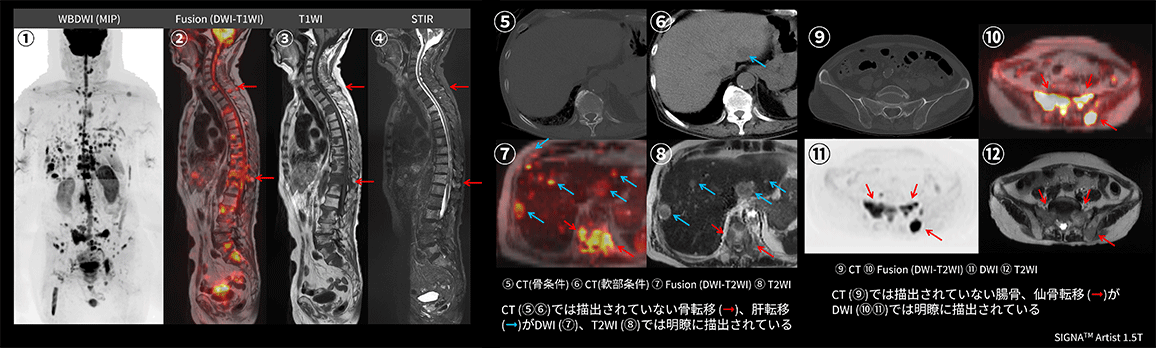

Case3 呼吸器内科:肺癌の骨転移検索目的

70代、男性。肺癌に対して放射線化学療法後、腰痛出現するも単純CTでは原因を特定できず、WBDWIを施行した。WBDWI MIP(①)では、頸椎、胸椎、腰椎、鎖骨、骨盤骨、大腿骨など多発骨転移と肝転移も認められる。②~④の矢状断像では、WBDWI MIP(①)で椎体に重なっていた棘突起の転移、CT(⑤⑨)では描出困難な腰椎、仙骨、腸骨転移(➞)がMRI(⑦⑩)では明瞭に描出されている。まさに骨梁間型骨転移の典型例である。単純CTでは描出されていない肝転移(➞)においてもDWI(⑦)、T2WI(⑧)では明瞭に描出されている(図12)。依頼医からは肺癌は骨梁間型骨転移が多く認められるため、肺癌の骨転移検索にWBDWIは非常に有用であると評価が得られた。

Architect_Okazakishimin02_15.png図12 肺癌の骨転移検索目的